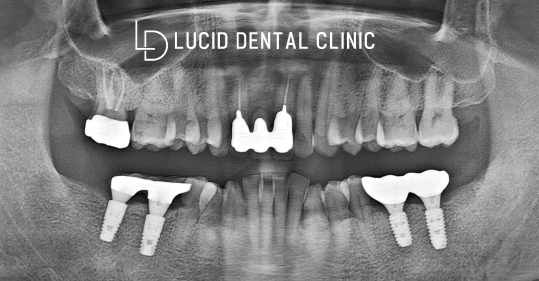

마무리 후 촬영한 파노라마 사진입니다.

치료가 모두 종료되었어도 사후 관리를

계속해서 시행하며 신경 써야 되는데요.